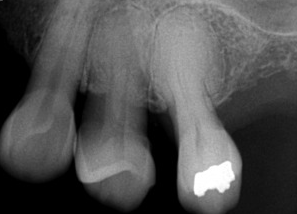

What is the dental anomaly seen in this image?

hypercementosis